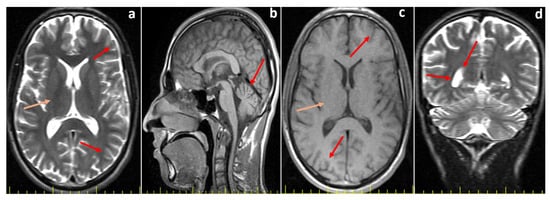

Further neurological assessments revealed that both affected siblings demonstrated impaired cognitive function but were able to follow simple commands and communicate effectively. Muscle strength in the upper and lower extremities was preserved, sensory responses were normal, and deep tendon reflexes were hypoactive. There were no signs of extremity spasticity, pathological reflexes, or seizure activity. The Romberg test was positive, and both dysarthria and dysdiadochokinesia were present. Cranial MRI of the elder sibling (P1), performed at the age of 20, showed mild cerebellar atrophy (Figure 1), whereas the MRI of the younger sibling (P2), obtained at the age of 12, revealed no structural abnormalities (Figure 2). Eye movements were normal in both cases, and no tongue fasciculations or aphasia were observed. Additionally, plasma creatine kinase (CK) levels were within normal limits for both patients.

Figure 2.

Cranial MR images of the younger sibling (Proband 2, P2) at 12 years of age. (a) T2-weighted axial image demonstrates normal cerebral sulci and gyri (red arrows). (b) T1-weighted axial image demonstrates normal cerebral sulci and gyri (red arrow) and basal ganglia (orange arrow). (c) T2-weighted axial image demonstrates a normal corpus callosum (orange arrow), with no evidence of cerebellar atrophy (red arrow).